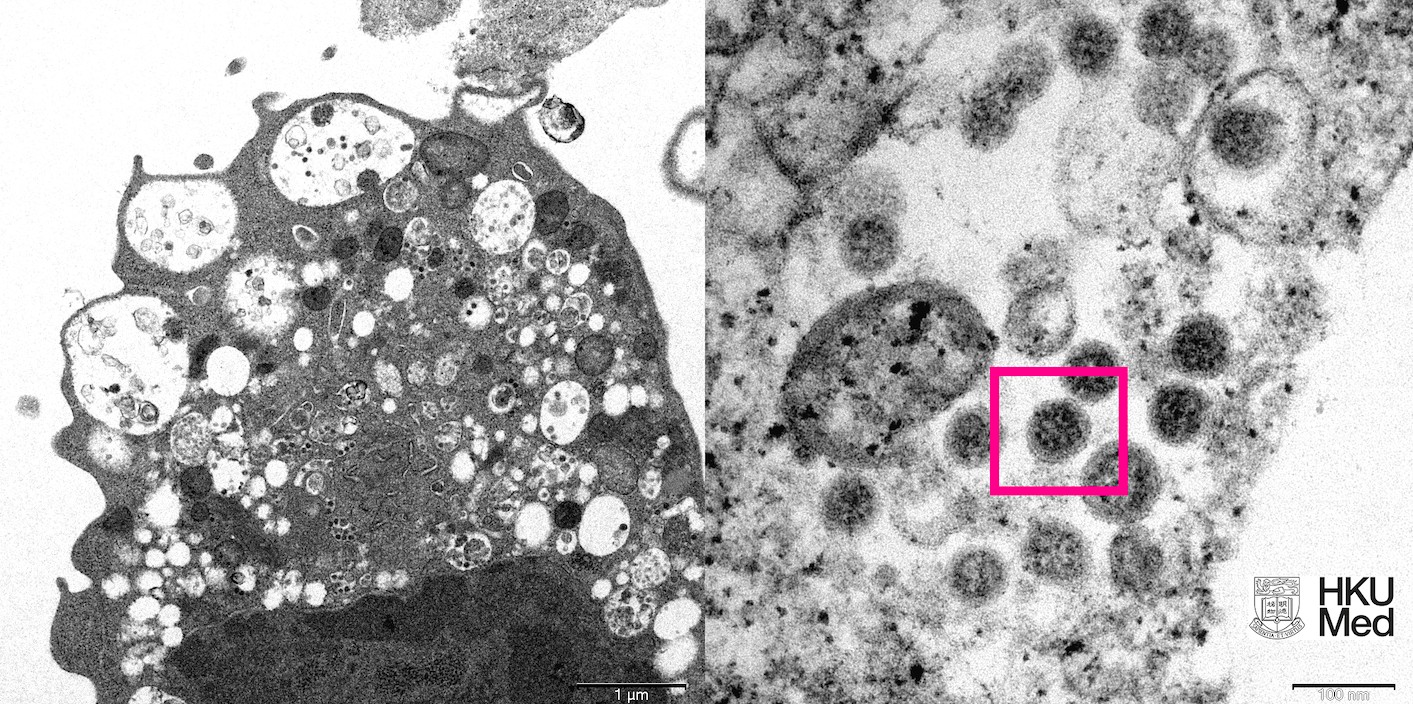

Agência disse também que a variante tem rápida disseminação. Imagem destaca variante ômicron do coronavírus feita com um microscópio

Cortesia Faculdade de Medicina da Universidade de Hong Kong